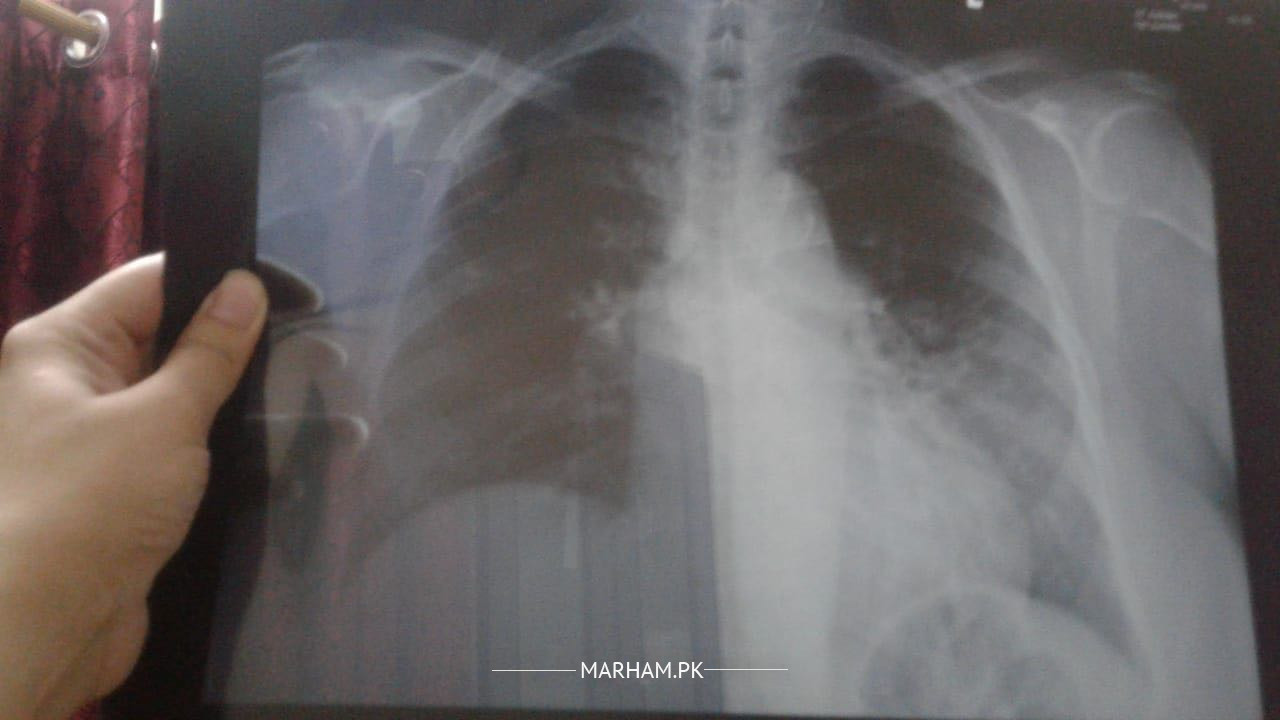

Asking on behalf of my mother she is 54 yrs old. She had a covid in December 2020, it was so severe and treated at home by having instructions from family dr. Now she is still having a cough covid tested again it’s negative. I am attaching her xray report and pictures. If any could suggest some remedies or medicine. Had fever but after taking Panadol currently she doesn’t have a fever. But feeling weakness. Today she started cefiget 400Mg

This her current xray